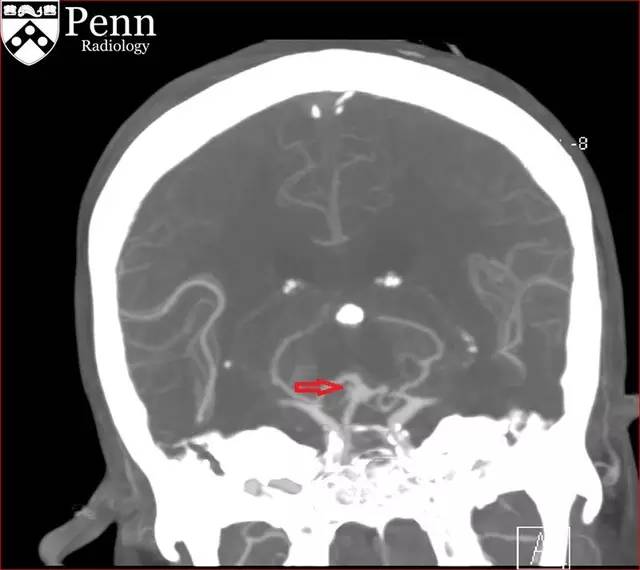

图 5 CTA 可见囊样动脉瘤(红色箭头)

图 6 CTA 可见囊样动脉瘤(红色箭头)

CTA 示右侧右小脑上动脉一大小为 2.0 x 2.0 x 1.2 mm 的动脉瘤。